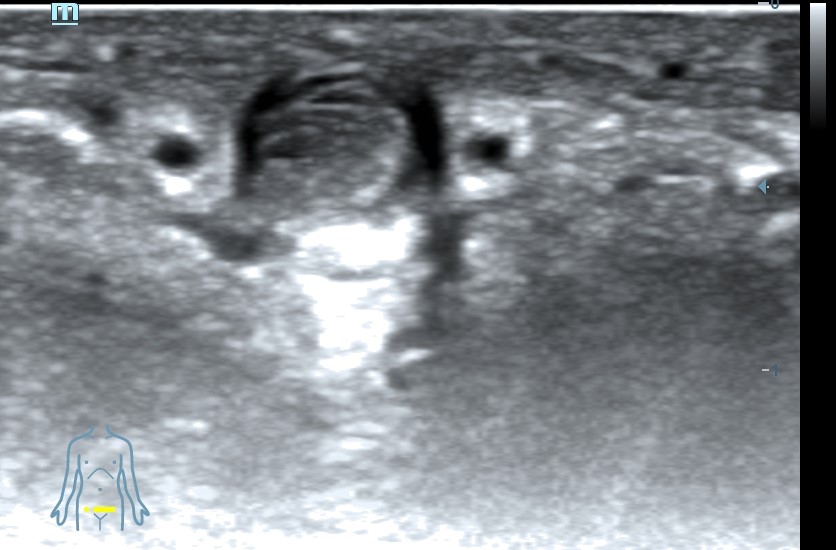

Ecografía clínica pene: se visualiza vena dorsal rellena de material hipoecogénico heterogéneo, no compresible, no flujo con Doppler color.

Diagnóstico: Trombosis vena dorsal del pene.

La trombosis de la vena dorsal del pene (o flebitis de Morton) es una rara entidad que cursa con dolor e induración dorsal, la etiología puede ser traumática, neoplásica, por excesiva actividad sexual o prolongada abstinencia. Puede cursar de forma aguda, subaguda o crónica. Para el diagnóstico, el estudio de imagen ideal es el eco-Doppler y el tratamiento se basa en antiinflamatorios y antibióticos en caso de infección. Pueden ser útiles sustancias heparinizantes locales reservándose el manejo quirúrgico con trombectomía o resección de la vena dorsal para casos persistentes.